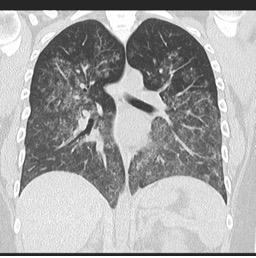

o   Високорезолуциона компјутерска томографија (ВРКТ): Приказује дифузне „ground-glass“ замућености и депозицију hemosiderina

o   HRCT: Приказује интерстицијалну болест плућа и „ground-glass“ замућења

o   HRCT: дифузне „ground-glass“ замућености и алвеоларна консолидација.

Дифузно алвеоларно крварење услед васкулитиса

Извор: radiopaedia.org